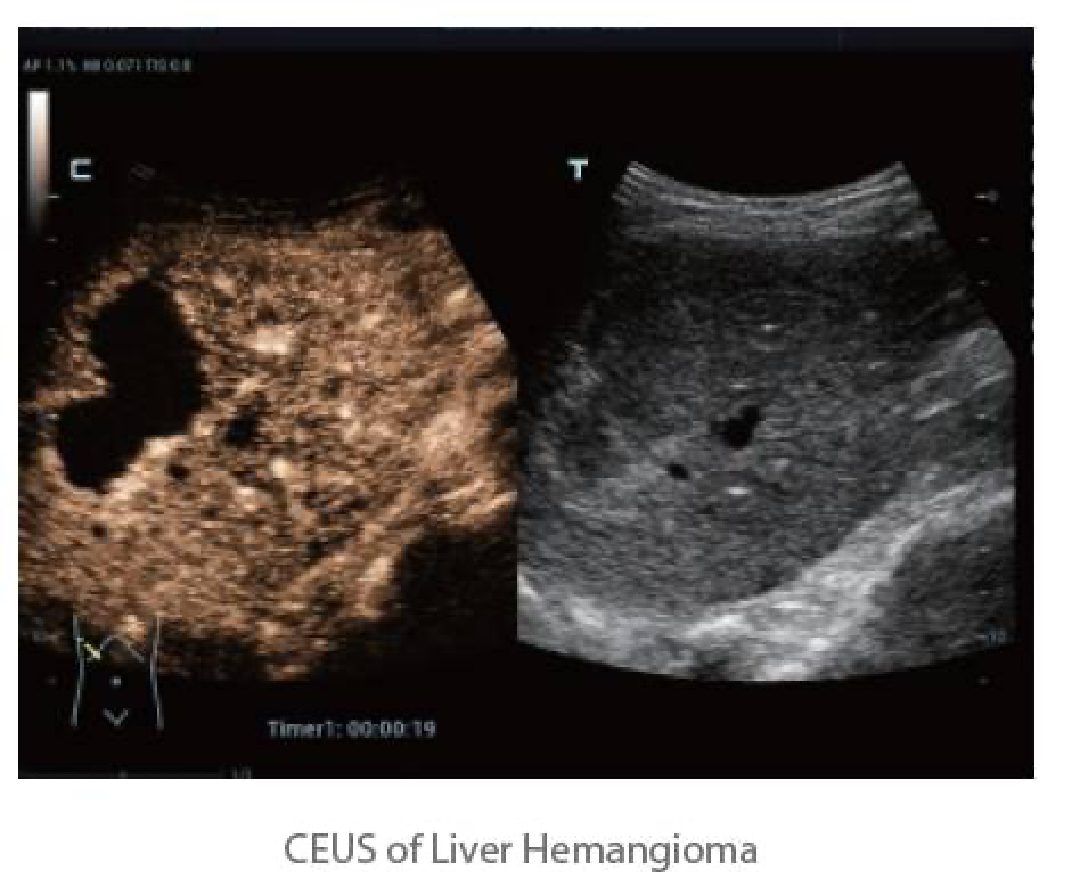

UWN+(Ultra-Wideband Non-linear Plus) CEUS enables the Resona 6 to detect andutilize both 2nd harmonic and non-linear fundamental signals, generating significantly enhanced CEUS images, resulting in greater sensitivity of minor signals and longer agent duration with lower MI.